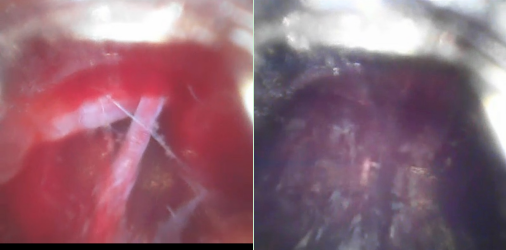

术中,团队通过导管内置高清摄像头精准避开血管,直达血肿中心,结合C臂CT实时导航动态调整穿刺路径,误差控制在1毫米以内。手术仅耗时30分钟,术后第3天患者语言功能明显恢复,右侧肌力显著改善,血肿清除率达95%。该技术的成功应用,标志着脑出血微创治疗迈入“精准、高效、安全”的新阶段。

术中导航:C臂CT三维成像锁定穿刺路径

可视导管:镜下避开血管,直达血肿中心